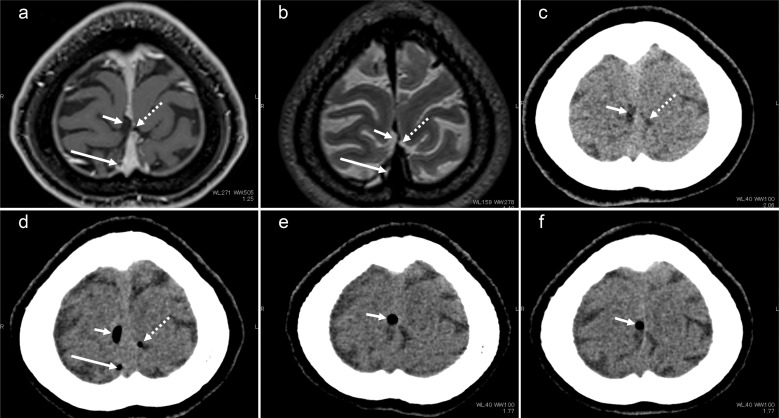

术后颅内空气通常减少,可能与脑脊液(CSF)和静脉循环合并。我们的研究报告了两个经蝶窦手术病例,突出了蛛网膜肉芽(AG)潜在的空气吸收-一个未被充分探索的现象。长期以来,AG一直被认为是脑脊液吸收的关键,但最近的观点表明,AG在废物清除、神经炎症和神经免疫中发挥着重要作用。这些病例可能会激发对AG在神经流体动力学中的多方面作用的新研究,并有可能进一步阐明AG的功能。

Postsurgery intracranial air usually diminishes, presumably merging with cerebrospinal fluid (CSF) and venous circulation. Our study presents two transsphenoidal surgery cases, highlighting potential air absorption by arachnoid granulation (AG)-an underexplored phenomenon. AG has long been deemed pivotal for CSF absorption, but recent perspectives suggest a significant role in waste clearance, neuroinflammation, and neuroimmunity. These cases may stimulate renewed research on the multifaceted role of AG in neurofluid dynamics and potentially elucidate further AG functions.